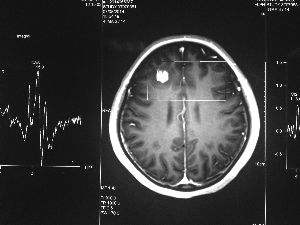

方框亮點為CT片顯示的異物

20歲的張敏,在江蘇蘇州上大學。今年1月份張敏放寒假在家,忽然摔倒在地,渾身抽搐,口吐白沫。20分鐘后,她才醒過來,對剛才發(fā)生的事情,一無所知。家里人將張敏送到醫(yī)院,醫(yī)生認為,雖然癥狀很像癲癇,但頭顱的CT檢查沒有發(fā)現(xiàn)任何異常。

今年6月份,張敏在宿舍休息時,又發(fā)起了癲癇,也是口吐白沫,渾身抽搐。送到蘇州一家大醫(yī)院,頭顱核磁共振檢查出,張敏大腦右額葉處有一處病灶,也就是大腦額頭處有個東西。

專家認為有可能是腦瘤,但也有可能是其他的東西,具體是什么,卻沒有辦法進一步判斷。醫(yī)院開了一點控制癲癇的藥物,讓張敏服用,并叮囑隨時復查。

腦袋里的東西,到底是腫瘤還是其他什么東西,這個謎像個石頭一樣,壓得張敏一家人喘不過氣。7月份,張敏一家又來到南京腦科醫(yī)院求醫(yī),第三次檢查后,醫(yī)生覺得很像是寄生蟲。不過,影像的檢查,只能作為醫(yī)生推測的依據(jù),具體是什么,只有手術拿出來后才能知道。